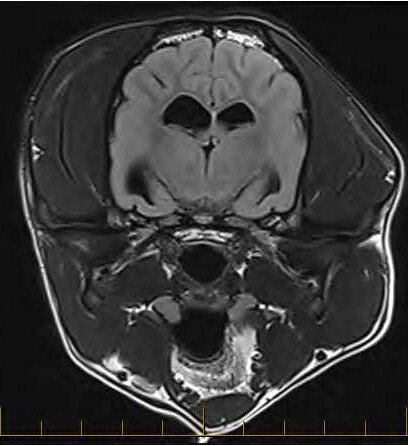

Currently, MRI is considered the best way to image the nervous system. It provides unparalleled detail of the:

- Brain (detecting tumors, inflammation, or strokes)

- Spinal Cord (identifying slipped discs or nerve compression)

- Surrounding Soft Tissues